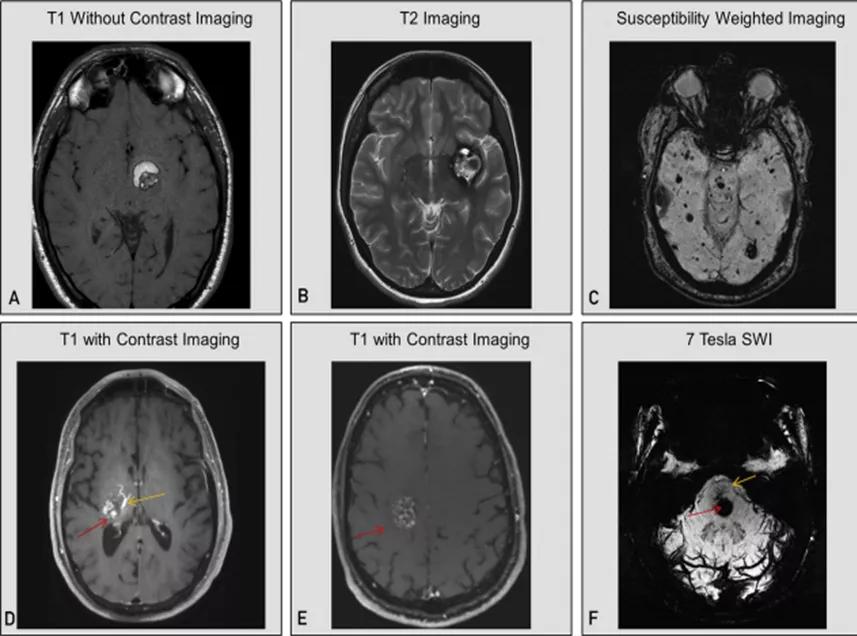

头颅CT通常在紧急情况下进行,可显示海绵状血管瘤的出血或钙化。然而,头颅CT对诊断海绵状血管瘤的敏感性和特异性较差。脑部MRI,最好是3T的标准序列和SWI序列,是首选的诊断方法。

图5:颅内海绵状血管瘤在不同核磁序列中的表现特点:A为T1序列(非增强),提示近期出血的海绵状血管瘤;B为T2序列,提示陈旧性出血的海绵状血管瘤;C为SWI序列,提示家族型多发海绵状血管瘤;D为T1增强序列,提示合并发育性静脉异常的海绵状血管瘤;E为T1增强序列,提示海绵状血管瘤病灶轻度、斑片状强化特点;F为7T-SWI序列,提示合并发育性静脉畸形的海绵状血管瘤

T1加权序列可显示与近期亚急性出血有关的高信号(图5A),如果近期没有出血,病灶可能显示为等信号。T2加权序列中病变中央区一般呈网状,类似于桑葚,病变周围呈提示含铁血黄素环的低信号(图5B)。

含铁血黄素敏感序列,包括梯度回波序列或SWI,通过显示海绵状血管瘤部位的低信号并可能显示额外的海绵状血管瘤(图5C)来帮助确诊。无发育性静脉异常合并的多个海绵状血管瘤可能提示家族性,但也可能见于辐射诱发的患者当中。除了T1加权增强MRI之外,SWI可以帮助识别相关的发育性静脉异常(图5D)。

在增强序列中,海绵状血管瘤可能会呈弥漫性轻微强化(图5E),但不会明显强化或环形强化。后者如果伴有SWI序列的改变,则更多的是提示出血性转移瘤、感染性进程,或者很少是炎症/脱髓鞘性疾病。